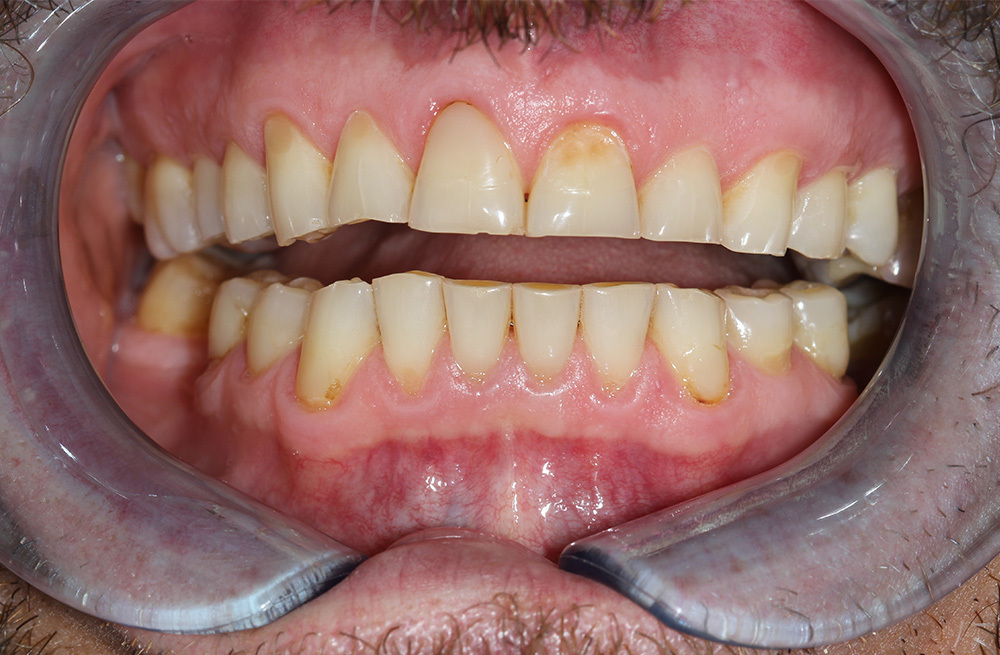

Эстетическая реабилитация винирами при генерализованной стираемости зубов